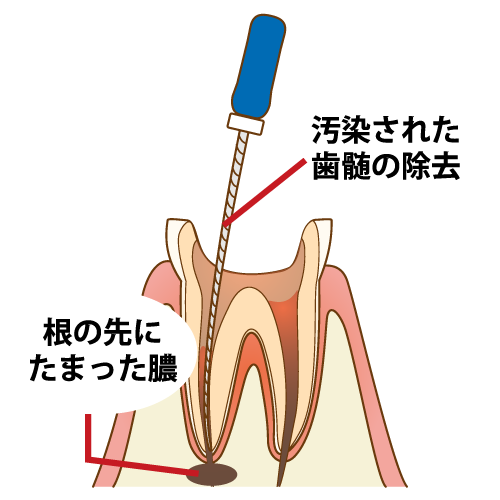

神経が死んでから時間が経過すると歯の根っこの先に膿がたまった状態になってしまいます。すぐに痛みが出ないこともあり、自分で気がつくことは少なく、レントゲンなどで発見される事がほとんどですが、放っておくと痛みや腫れが起こるため根管治療が必要となります。

まず先に虫歯を全て取り除きます。虫歯があるとそこから菌が根管内や神経に繁殖するので、菌に汚染された神経など全て除去します。歯の根っこの中にある根管のさらに中の神経を細い針のような器具、あるいは器械で取っていきます。